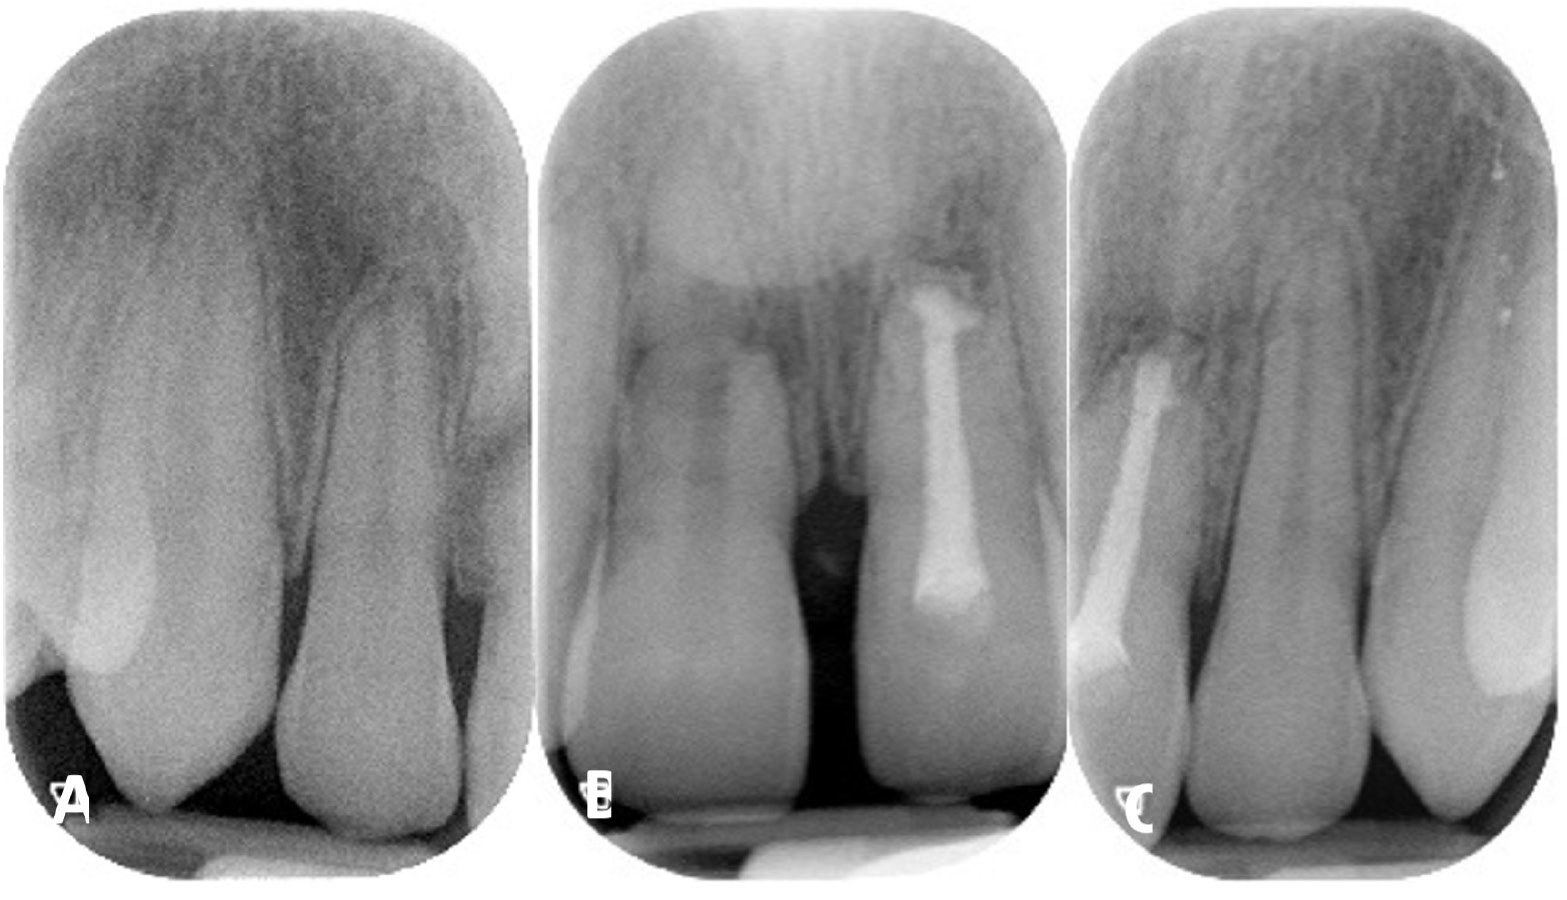

The radiological aspect of no healing is shown in Figure 1. No healing occurs if the pulp of the coronal fragment becomes necrotic and infected, with interposition of granulation tissue that extends into the adjacent bone and evidence of radiolucency extending laterally. Figure 1 also shows external inflammatory resorption in the apical third of the root and signs of bone periapical radiolucency.

Cone beam computed tomography (CBCT) may often be required as a follow-up to assess the involvement of surrounding tissues, the amount of external and internal root resorption on the involved teeth, the anatomy of the root fracture of the apical third, and displacement of the coronal segment. Figure 2 and Figure 3 illustrate CBCT parasagittal images that confirm the results of the intraoral radiographs. The diastasis between the coronal and apical fragments of #11 appear to be more evident on the fracture line and the presence of a “new apical foramen” is highlighted. In addition, areas of external inflammatory resorption on the apical fragment are evident and the fracture line appears jagged. The images relating to #21 appear suggestive for external inflammatory resorption, particularly on the vestibular side, which is the site of concomitant bone inflammation in the parasagittal image #48. Internal pulp resorption can also be observed at the apical third of the root.

The inflammatory reaction that results in no healing is caused by the infection of the root canal system. In cases of root fracture, the infection occurs at the fracture site rather than in the periapical tissues. The coronal fragment has a “new apical foramen,” which is now situated at the fracture line rather than at the apical end of the root. Root canal therapy of the coronal fragment can be initiated and calcium hydroxide intracanal medication can be administered. If symptoms persist (i.e., abscess episodes and/or mucous fistula), an apicoectomy can be performed. Figure 4 shows the fractured apical root fragment being removed and retrograde closure of the new root apex,25 which in one case is at the apicectomy level #11 and in the other at the root fracture line #21.26, 27